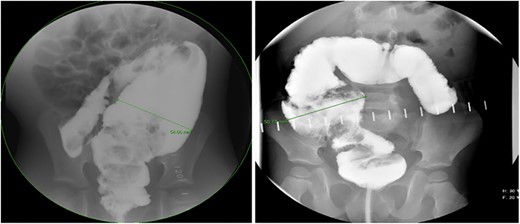

There is a subset of patients in whom primary transanal pull-through in those >2 years of age at the time of surgery is possible. While a previous case series reported that 18.8% of their late-diagnosed HD patients underwent transanal primary pull-through, these authors did not describe outcomes or reasons for choosing the operative approach [7]. In case series, the characteristics of patients who were able to undergo primary transanal-only pull-through include overall earlier age (2–6 years) vs. those diagnosed later. On contrast enema, they exhibited a limited degree of megacolon (Figs 1 and 2). Proximal colonic dilation was absent in all four patients that we felt were good candidates for a transanal-only approach. However, proximal colonic dilation (proximal of the sigmoid) was visualized in 15 patients, and therefore, a transanal-only approach was not offered. The ability to identify a clear transition zone low in the rectosigmoid was also observed in each patient. Finally, the ability to empty the colon preoperatively whether through laxatives or rectal irrigations was also present.

Representative contrast enema study of an older child with a large amount of proximal colonic dilation of the sigmoid and descending colon, seen here across multiple views during contrast enema (Not a candidate for transanal only).

Prior to beginning the pull-through, the colon should be irrigated to make sure that any retained fecal matter has been cleared. Careful assessment of the transition zone and confirmation of minimal proximal colonic dilatation allows for prone-only positioning and a transanal-only approach (Fig. 1). The Lone Star retractor and full-thickness dissection begin 1.0 cm proximal to the dentate line in the Swenson plane. Biopsies should be taken in a single line so as not to lose orientation [8] and 10–15 cm past the positive biopsy for ganglion cells to assure that normal caliber colon is reached before performing the anastomosis. Challenges with the transanal-only approach occur when there is a large amount of proximal colonic dilation, and therefore, in this instance, we recommend a laparoscopic approach for intraoperative mobilization of the descending and proximal colonic mobilization off the left retroperitoneum [9]. If at the time of anastomosis of the dilated ganglionated bowel, anal caliber size discrepancy is encountered a trick can be employed by placing four quadrant sutures and then bisecting each quadrant again and again with interrupted sutures [10].